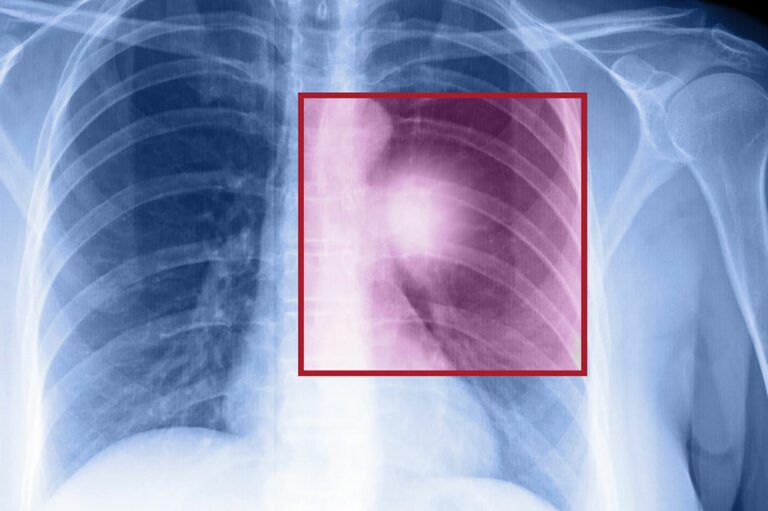

Lung cancer – Types, symptoms, and causes

When the cells in the lungs begin to abnormally multiply and grow, it results in cancer. Lung cancer is one of the leading causes of death in the world. And the risk of suffering from this life-threatening disease is even higher when one is a smoker. Herein, we discuss the various factors that come into play when it comes to lung cancer. Symptoms of lung cancer Usually, lung cancer does not present any symptoms or signs in the early stages. However, as the disease progresses, one may notice Headache Bone pain Loss in weight Hoarse voice Chest pain Shortness of breath Coughing of blood A new cough that persists One should consult a doctor if they notice these signs. If someone is unable to quit smoking, they should visit a medical practitioner for quitting techniques to help avoid this disease. Types of lung cancer There are two kinds of lung cancer: Non-small cell lung cancer This is a catchall term that includes many varieties of this disease, like large cell carcinoma, squamous cell carcinoma, and adenocarcinoma. Small cell lung cancer This happens mainly to people who are heavy smokers, and it’s rarer than non-small cell lung cancer. Risk factors of lung cancer Various factors put you at risk of getting this disease.